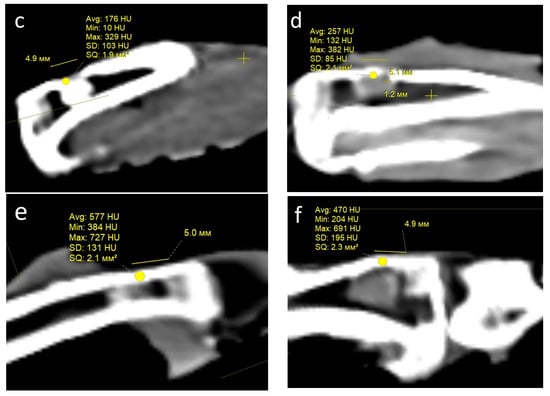

Condition of the defect area and computed tomography (CT) examination. One month after the operation, all rabbits in both groups showed signs of regeneration of the inflicted experimental bone defect in the form of a decrease in its size by 1–2 mm. The size of the defect, determined by CT measurements on the day of surgery, corresponded to the intraoperative measurements. At the CT densitometry assessment of the area after 1 month, the Hounsfield index among all rabbits in the control group (grafted osteoplastic matrix) was 69–271 HU. The average values of the X-ray density of the entire volume of the graft in the animals in this group were 142–229 HU, which indicated the heterogeneous nature of the cavity contents (Figure 8a). The values of this parameter in the experimental group (hybrid polymer) ranged from 15–89 HU. The average values of the X-ray density of the entire volume of the graft in the animals in this group were 31–67 HU (Figure 8b). This very insignificant scattering of values indicated the homogeneity of the graft. In the cortical bone structures adjacent to the defect, the Hounsfield index value was 680–720 HU.

Figure 8.

CT scan—section through the center of the implant in the sagittal direction, observed: at 1 month: (a) control, (b) experiment; at 2 months: (c) control, (d) experiment; at 6 months: (e) control; (f) experiment.

In the animals removed after 2 months, a further decrease in the size of the defect was seen, decreasing to an insignificant size of 1–2 mm. All animals in the control group (grafted osteoplastic matrix) had absolute values of the Hounsfield index from 10–457 HU. The average values of the X-ray density of the entire volume of the graft in the animals in this group were 171–231 HU (Figure 8c). The minimum value in the experimental group (hybrid polymer) was 96 HU, the maximum was 643 H. The average values ranged from 195–453 HU (Figure 8d). The measurements did not reveal any pathological changes in the cortical bone structures adjacent to the defects.

After 6 months, complete recovery of the applied defect was demonstrated in all animals in both groups. However, the Hounsfield index in the control group (grafted osteoplastic matrix) ranged from −60 to 910 HU and continued to demonstrate the heterogeneity of the graft tissue, along with occasional increases above the usual values for shin bone. The average values ranged from 305–577 HU (Figure 8e). The values of the X-ray density of the central part of the graft in the experimental group (hybrid polymer) ranged from 204–814 HU. The average values ranged from 426–615 HU (Figure 8f).

The dynamics of the changes in X-ray density in the defect area are shown in Table 2.

Table 2.

Hounsfield index values (in HU).

Therefore, the CT data, which includes CT densitometry of the central area of the graft, indicate that the processes of reparative regeneration in the animals in the control and experimental groups differed to some extent. In the control group, at all assessment points, the density of the graft was convincingly heterogeneous, and included areas where minimal X-ray shadow intensity persisted for 6 months. The graft placed into the bone defect in the rabbits in the experimental group demonstrated a stable increase in X-ray density, together with a less significant scatter between the minimum and maximum values of the X-ray shadow intensity.

Consequently, based on the CT image analysis, the authors determined the development of a more uniform structure; therefore, it was concluded that there were more active regenerative processes in the bone defects of the rabbits in the experimental group.